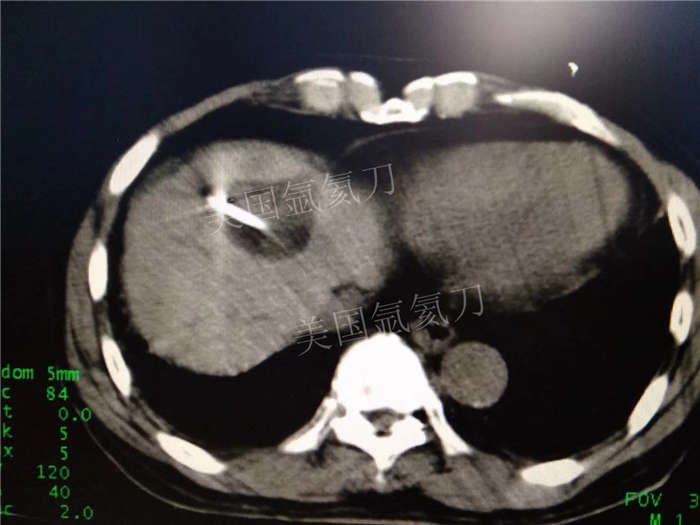

博罗人民医院乙状结肠癌术后肝转移化疗后冷冻消融